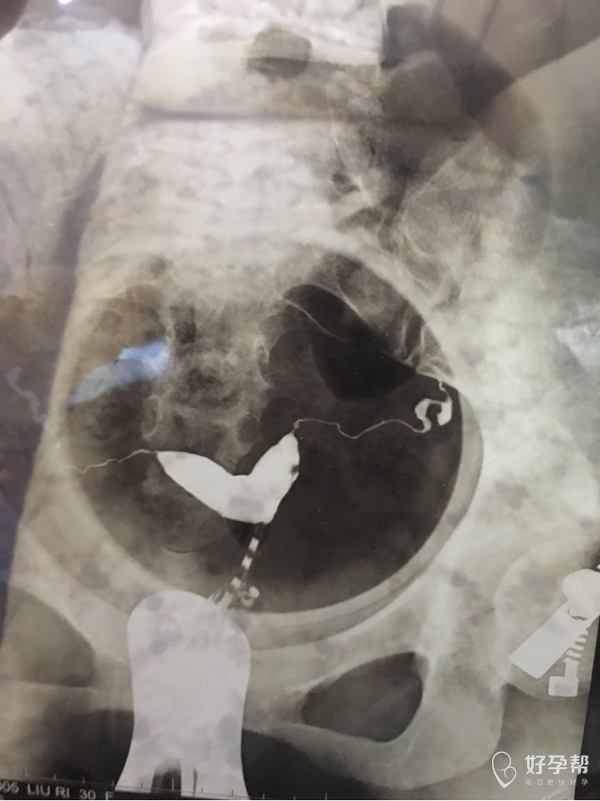

我怀孕五十一天,今天去复查胎停育,阴氏B超显示双角子宫[流泪][流泪][流泪][流泪]麻烦医生帮忙看看我这个造影时显示的子宫双角子宫严重吗?